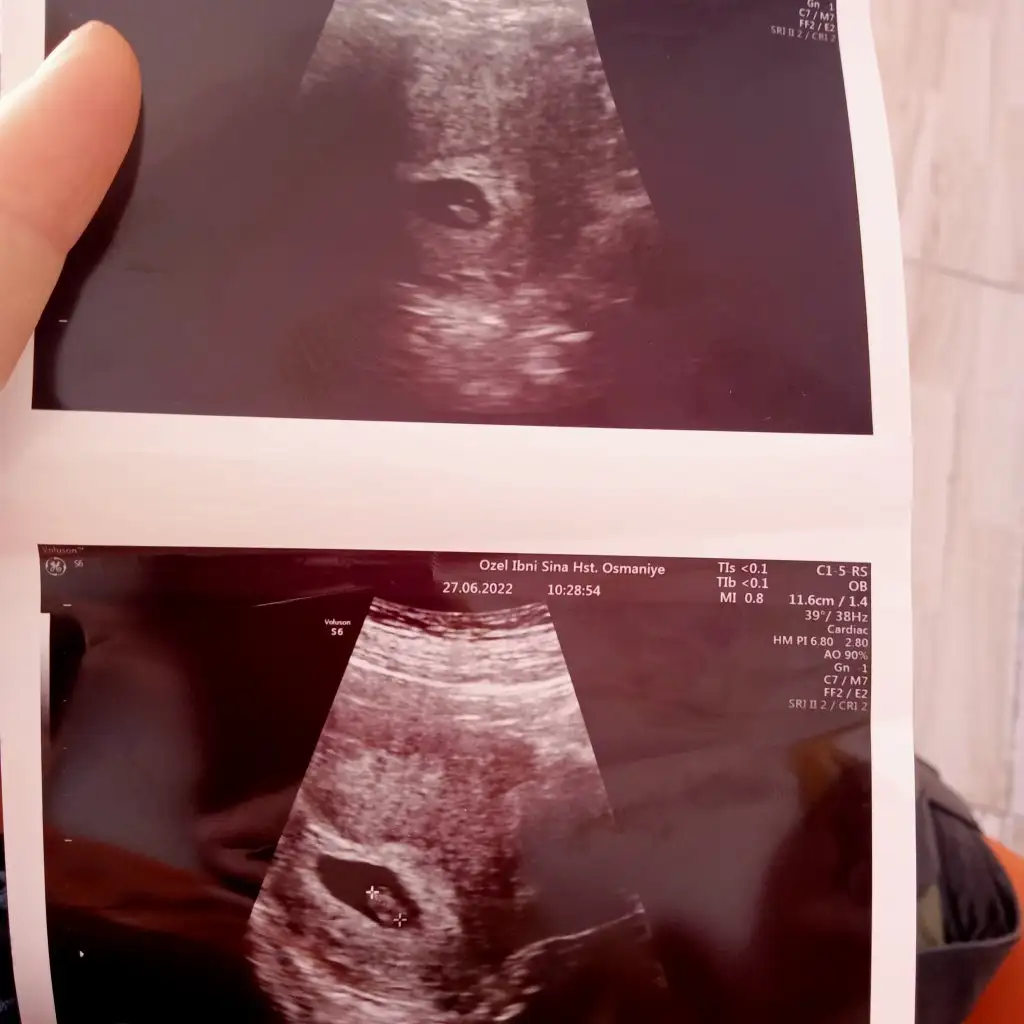

Bu da karın utrasyonu 7 haftapaşa gibi

tuhafBu da karın utrasyonu 7 hafta